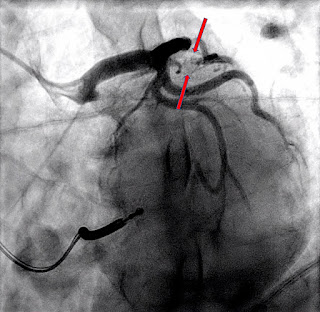

Ангиограмма:

Первичное ЧКВ при остром переднебоковом ИМпST.

Виновником является 100% стеноз в проксимальном отделе ПМЖВ.

Виновник поражения был уменьшен до 0% баллоном и стентирован.

90% устьевые стенозы ПМЖВ-D1 уменьшены баллоном до 35% и выполнено стентирование.